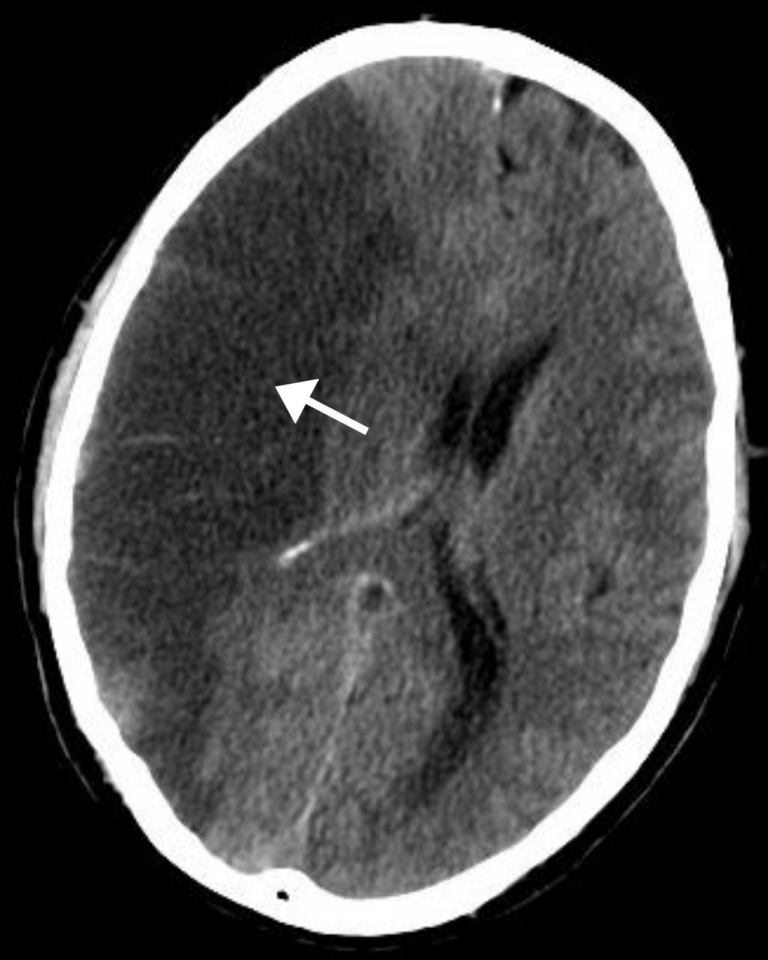

Ишемический инсульт (инфаркт мозга) на КТ